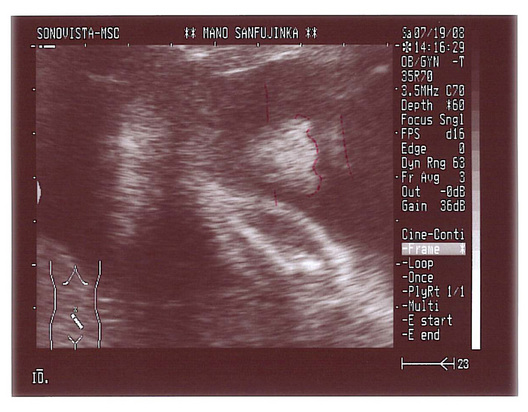

25週3日 エコー

妊娠25週3日 25w3d の超音波 エコー 写真

25週3日のエコー写真 Acchan To Fucchan